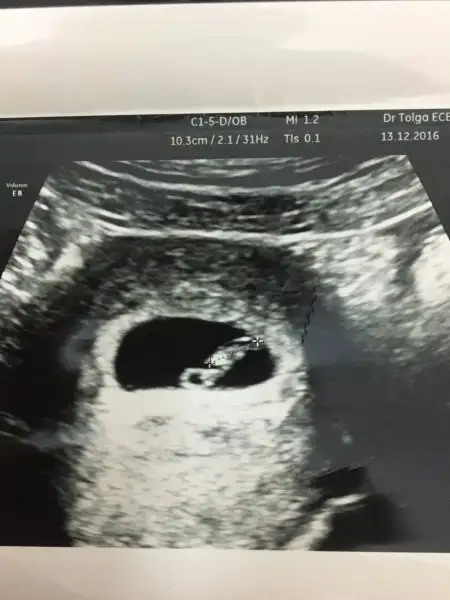

KIZLAR MERHABA 7+3 RESMIMIZ YORUMLAR MISINIZZ

BIRINDE SOLDA GORNUYOR. ERKEK DIYORLAR SOL OLUNCA AMA BILEMIYORUM TAMDA. KALP ATISI NASIL ?

Canım kalp atışı varmı yokmu bilemedi dr, bebek çok kğçük dedi, atan bişey var ama kalbin atımımı yoksa senin vucudunun atımımı bellş değil dedi, bir hafta sonra tekrar gideceğim

BENIMDE AYNI OLDU HATTA KORKTUK BISEYMI OLDU DIYE AMA MINIK OLDUGU ICINMIŞ :) 7. HAFTADA GİTTİK PIT PIT ATIYODU KALBI :) KALP ATIS HIZINA GOREDE KIZ ERKEK DIYORLAR AMA DOKTORA SORDUM ALAKASI YOK DEDI.140 ALTI ERKEK ÜSTÜ KIZ DEMISLERDI BNA. BENIMKIDE 105 :)